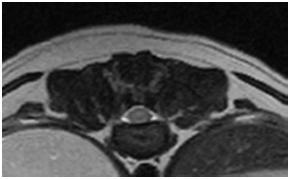

左は左前足と左後足が麻痺して歩けなくなったチワワの首のMRI画像、右が正常な子の画像です。

矢印の部分が脊髄ですが、左の画像はより白く映り、炎症が起こっているのが分かりました。 現在は治療によって症状は落ち着いています。

上は左前足と左後足が麻痺して歩けなくなったチワワの首のMRI画像、下が正常な子の画像です。

矢印の部分が脊髄ですが、左の画像はより白く映り、炎症が起こっているのが分かりました。 現在は治療によって症状は落ち着いています。 |